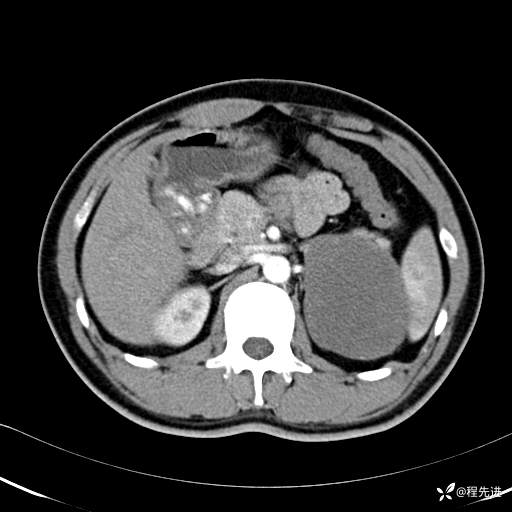

【腹盆】特别精彩病例|体检发现的左侧腹膜后占位期待您的精彩解读

患者年龄:25岁

简要病史:体检发现

CT平扫:(CT值:平扫,27HU,动脉期,27HU,门静脉期,31HU,平衡期,32HU)

CT增强:

平衡期: